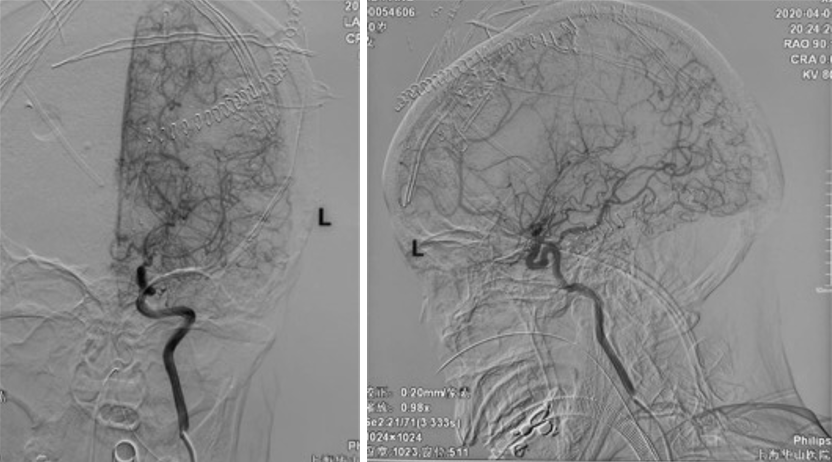

手术方案A:动脉瘤栓塞联合低流量搭桥。

手术方案B:动脉瘤切除联合低流量搭桥。

Postop dyna CT(-),GCS15,返回ICU,考虑择期行开颅手术。

有观点认为此类动脉瘤可以保守治疗,因为较小的脑室旁动脉瘤可能自发消退,但同样存在保守治疗的病例预后不佳[1-4]。深部动脉瘤通过血管内介入治疗往往能取得较好的疗效,治疗能否成功关键取决于载瘤动脉直径[5]。血管内栓塞通常是烟雾病患者脑室旁动脉瘤的首选方案,因为可以避免开颅手术对脑实质的损伤及相关的缺血事件发生[1]。在一项病例系列研究[6]中,血管内栓塞成功治疗了7例(88%)烟雾病伴脑室旁动脉瘤且无围术期并发症,其中6名患者在出院时完全康复(75%)。然而,烟雾病患者载瘤动脉往往十分迂曲,且动脉瘤容易破裂[5]因此血管内治疗往往充满挑战。显微手术夹闭是动脉瘤的传统治疗方法,但在治疗深部动脉瘤时,术中破裂的风险可能更高。微创手术如小骨窗和神经内镜已用于治疗颅内深部病变,并取得了不同程度的成功。

在本例病例中,针对脑室内动脉瘤,我们首选血管内治疗栓塞脑室旁动脉瘤,因为血管过于迂曲尝试失败。术后出现脑室内出血,于是启动备选方案,急诊在磁共振导航下通过endoport辅助进行动脉瘤切除,同时部分清除脑室内血肿并放置脑室外引流,降低远期脑脑积水的风险。随着神经内镜的普及,深部的脑血管病变的治疗方案有了更多的选择,而充分的术前评估与周全的手术方案规划是手术安全与成功的基石。